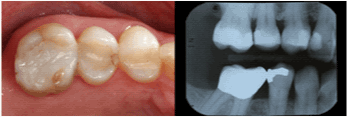

| Maxillary Left Second

Premolar |

12 |

74.4% |